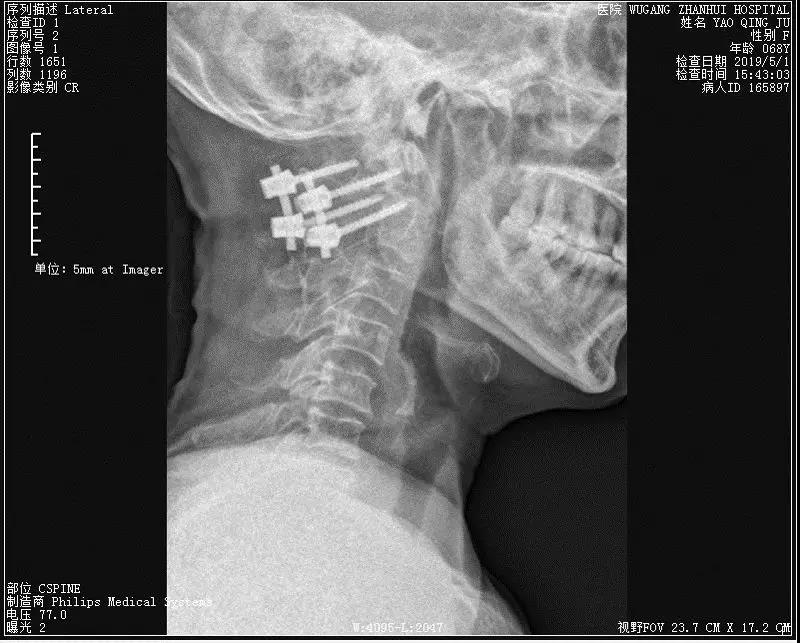

骨卫士特聘专家、原解放军307医院范海涛主任在会上分享了一例C2枢椎齿状突骨折并颈髓挫伤患者病例 。患者为67岁女性,因摔伤致四肢麻木,不能活动。

患者影像资料如下:

▲术前侧位及张口位